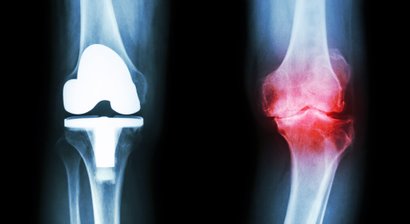

Knieprothese (Künstliches Kniegelenk) / Gonarthrose

Kniearthroskopie (Kniegelenkspiegelung)